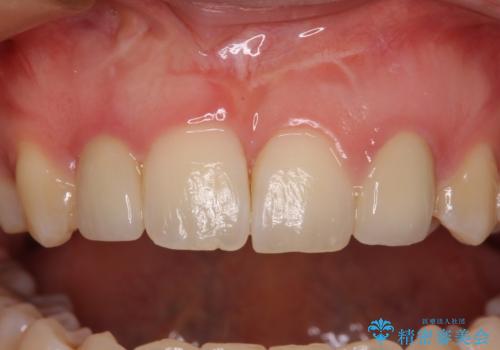

- 他院で矯正治療を終え、上顎前から2番目の歯の大きさを気にして来院された患者様です。

右側は小さく、左側は欠損により犬歯が前から2番に来ている状態でした。

矯正治療の段階で、矮小歯は前後にスペースが作ってあったため、極力左右対称の歯冠形態となるように補綴治療を行うこととしました。

歯根の太さや幅が左右で異なるため、歯肉ラインはどうしても左右非対称となってしまいますが、とても自然な口元となりました。